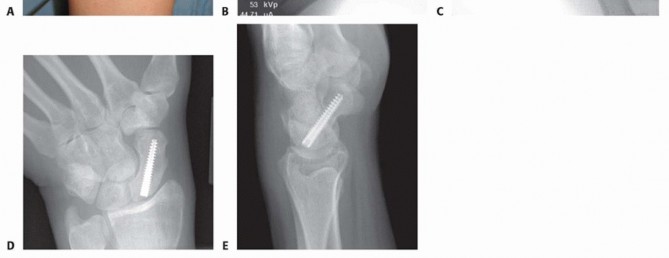

TECH FIG 2 • A-C. Before screw insertion, the position of the Kirschner wire must be changed from its position used for arthroscopy. The Kirschner wire should be driven from volar to dorsal until the distal end lies just beneath the articular surface of the scaphoid. D,E. Screw fixation of minimally displaced scaphoid fracture via the dorsal percutaneous technique. The screw tip should rest within 1 to 2 mm of the distal cortex. Excellent compression should be obtained with this technique.